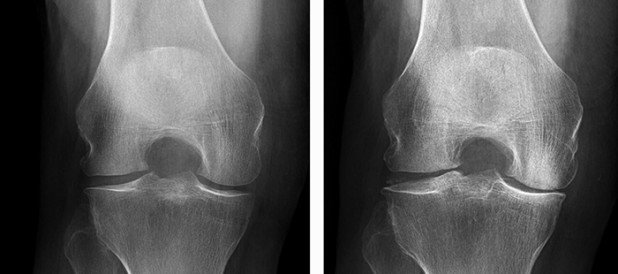

Die Antwort heisst: beides. Das MRI hat die Röntgendiagnostik in keiner Weise aus dem Repertoire verdrängt, sondern viel mehr ergänzt. So ist es nicht verwunderlich, dass bei den meisten Patienten nicht nur ein MRI, sondern auch ein Röntgenbild angefertigt werden muss, und zwar meistens zuerst Röntgen und erst dann das MRI. Die Beurteilung der Beinachse (X-Bein, O-Bein) kann nur radiologisch genau erfasst werden und hat ohne Zweifel einen Einfluss auf das Procedere.

Nicht selten wird das Röntgenbild bereits zu einer Diagnose führen. Dann kann man sich das MRI sparen, das dann aber bei einem unauffälligen Röntgenbild umso mehr indiziert ist. Ein «schmerzhaftes Knochenmarksödem» ist zum Beispiel eine solche klassische MRI-Diagnose, die im Röntgenbild auch bei starker Ausprägung unsichtbar bleibt (s. Abb. 1a und 1c).